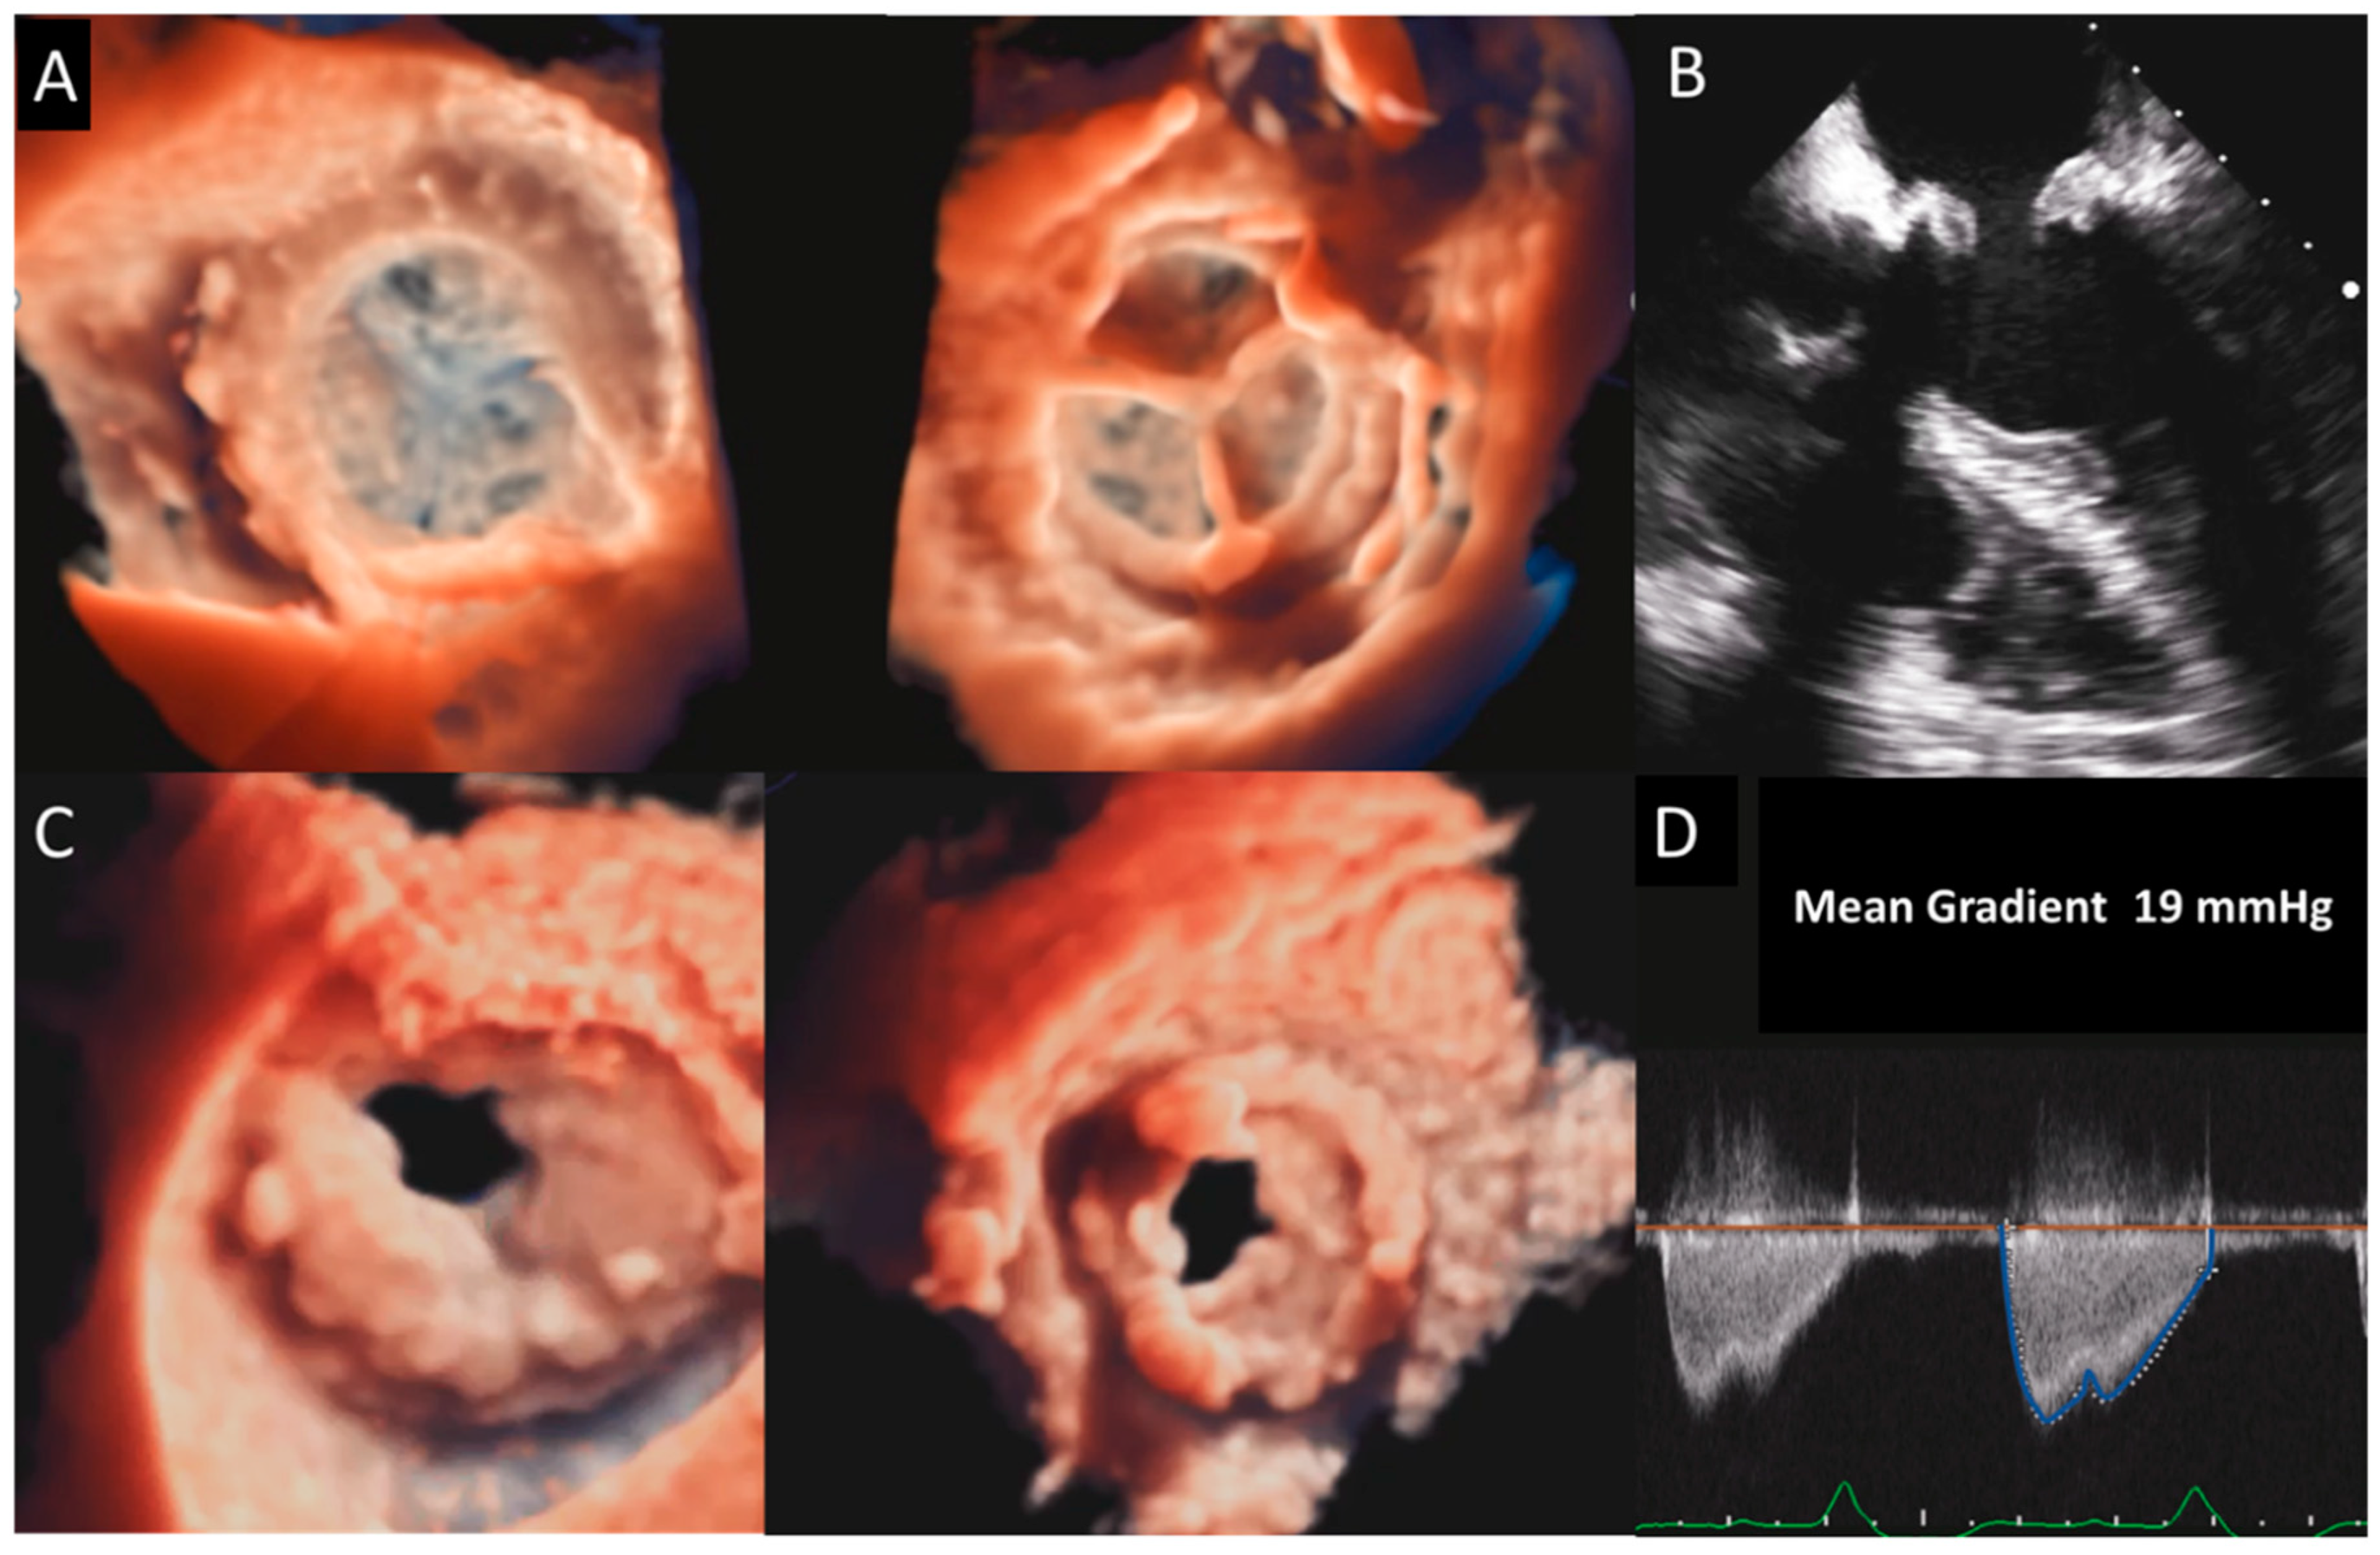

Figure 2. Biological mitral valve prosthesis degeneration. (A) TEE mid-esophageal views showing a marked thickening and degeneration of the MV prosthesis leaflets. (B)significant increase in the mean diastolic gradient of the prosthesis. (C) A 3D TEE surgical view of the MV prosthesis showing a marked reduction in the diastolic opening of the leaflets, as confirmed and further detailed by 3D TEE views from the LV or from the LA with the transillumination modality (D). MV, mitral valve; TEE, transesophageal echocardiography.